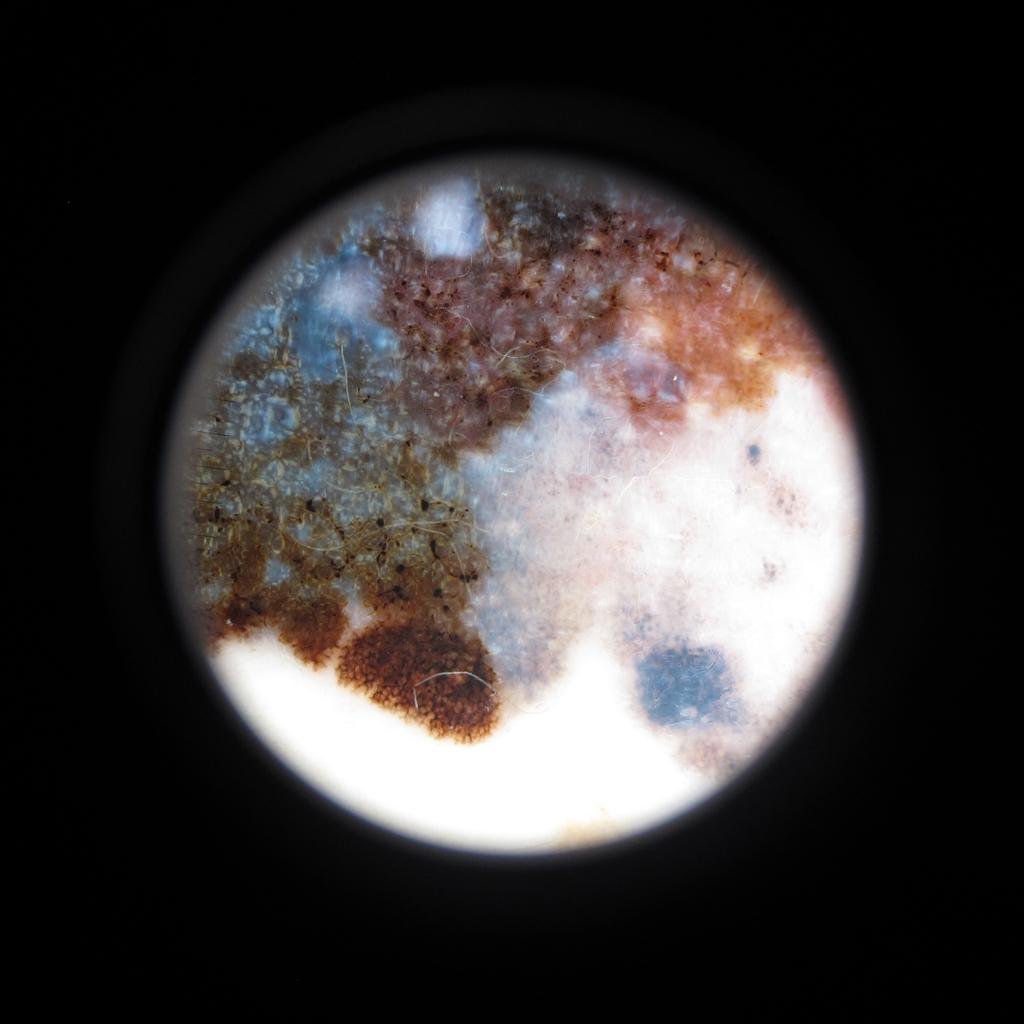

In this paper, we describe our method for the ISIC 2019 Skin Lesion Classification Challenge. The challenge comes with two tasks. For task 1, skin lesions have to be classified based on dermoscopic images. For task 2, dermoscopic images and additional patient meta data have to be used. A diverse dataset of images was provided for training, containing images from eight classes. The final test set contains an additional, unknown class. We address this challenging problem with a simple, data driven approach by including external data with skin lesions types that are not present in the training set. Furthermore, multi-class skin lesion classification comes with the problem of severe class imbalance. We try to overcome this problem by using loss balancing. Also, the dataset contains images with very different resolutions. We take care of this property by considering different model input resolutions and different cropping strategies. To incorporate meta data such as age, anatomical site, and sex, we use an additional dense neural network and fuse its features with the CNN. We aggregate all our models with an ensembling strategy where we search for the optimal subset of models. Our best ensemble achieves a balanced accuracy of using five-fold cross-validation. On the official test set our method is ranked first for both tasks with a balanced accuracy of for task 1 and for task 2.

Automated skin lesion classification is a challenging problem that is typically addressed using convolutional neural networks. Recently, the ISIC 2018 Skin Lesion Analysis Towards Melanoma Detection challenge resulted in numerous high-performing methods that performed similar to human experts for evaluation of dermoscopic images [15]. To improve diagnostic performance further, the ISIC 2019 challenge comes with several old and new problems to consider. In particular, the test set of the ISIC 2019 challenge contains an unknown class that is not present in the dataset. Also, the severe class imbalance of real-world datasets is still a major point that needs to be addressed. Furthermore, the training dataset, previously HAM10000 [16], was extended by additional data from the BCN_20000 [5] and MSK dataset [4]. The images have different resolutions and were created using different preprocessing and preparation protocols that need to be taken into account.

The main traning dataset contains dermoscopic images, acquired at multiple sites and with different preprocessing methods applied beforehand. It contains images of the classes melanoma (MEL), melanocytic nevus (NV), basal cell carcinoma (BCC), actinic keratosis (AK), benign keratosis (BKL), dermatofibroma (DF), vascular lesion (VASC) and squamous cell carcinoma (SCC). A part of the training dataset is the HAM10000 dataset which contains images of size that were centered and cropped around the lesion. The dataset curators applied histogram corrections to some images [16]. Another dataset, BCN_20000, contains images of size . This dataset is particularly challenging as many images are uncropped and lesions in difficult and uncommon locations are present [5]. Last, the MSK dataset contains images with various sizes.